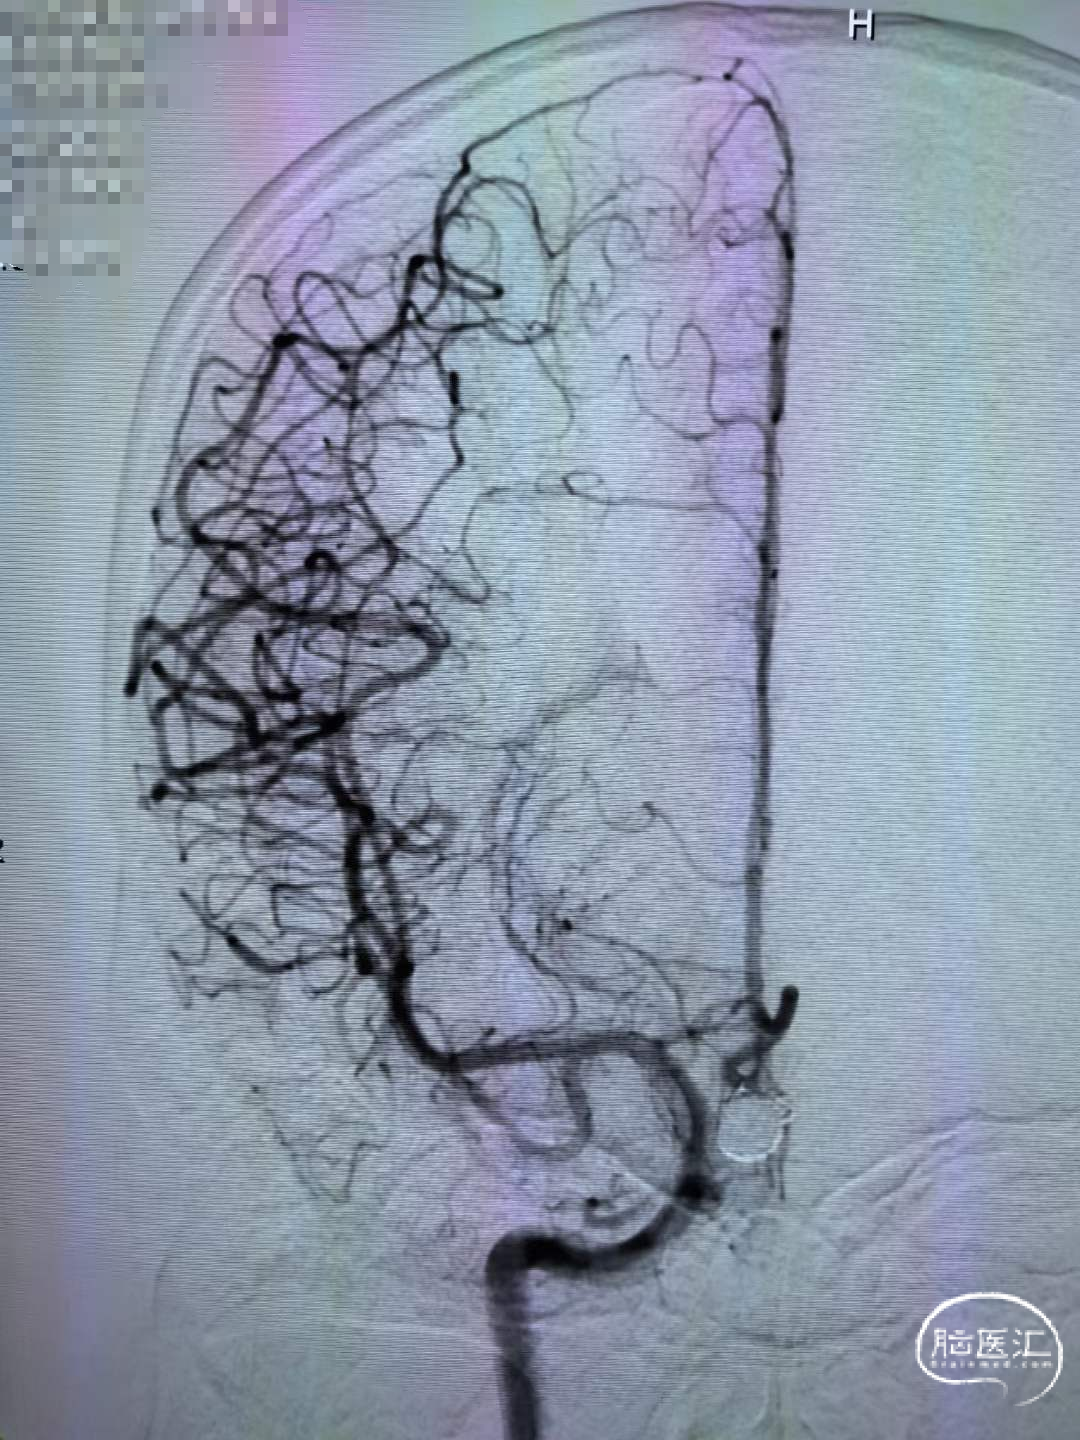

连续填塞五个弹簧圈致密栓塞动脉瘤,植入支架覆盖瘤颈。